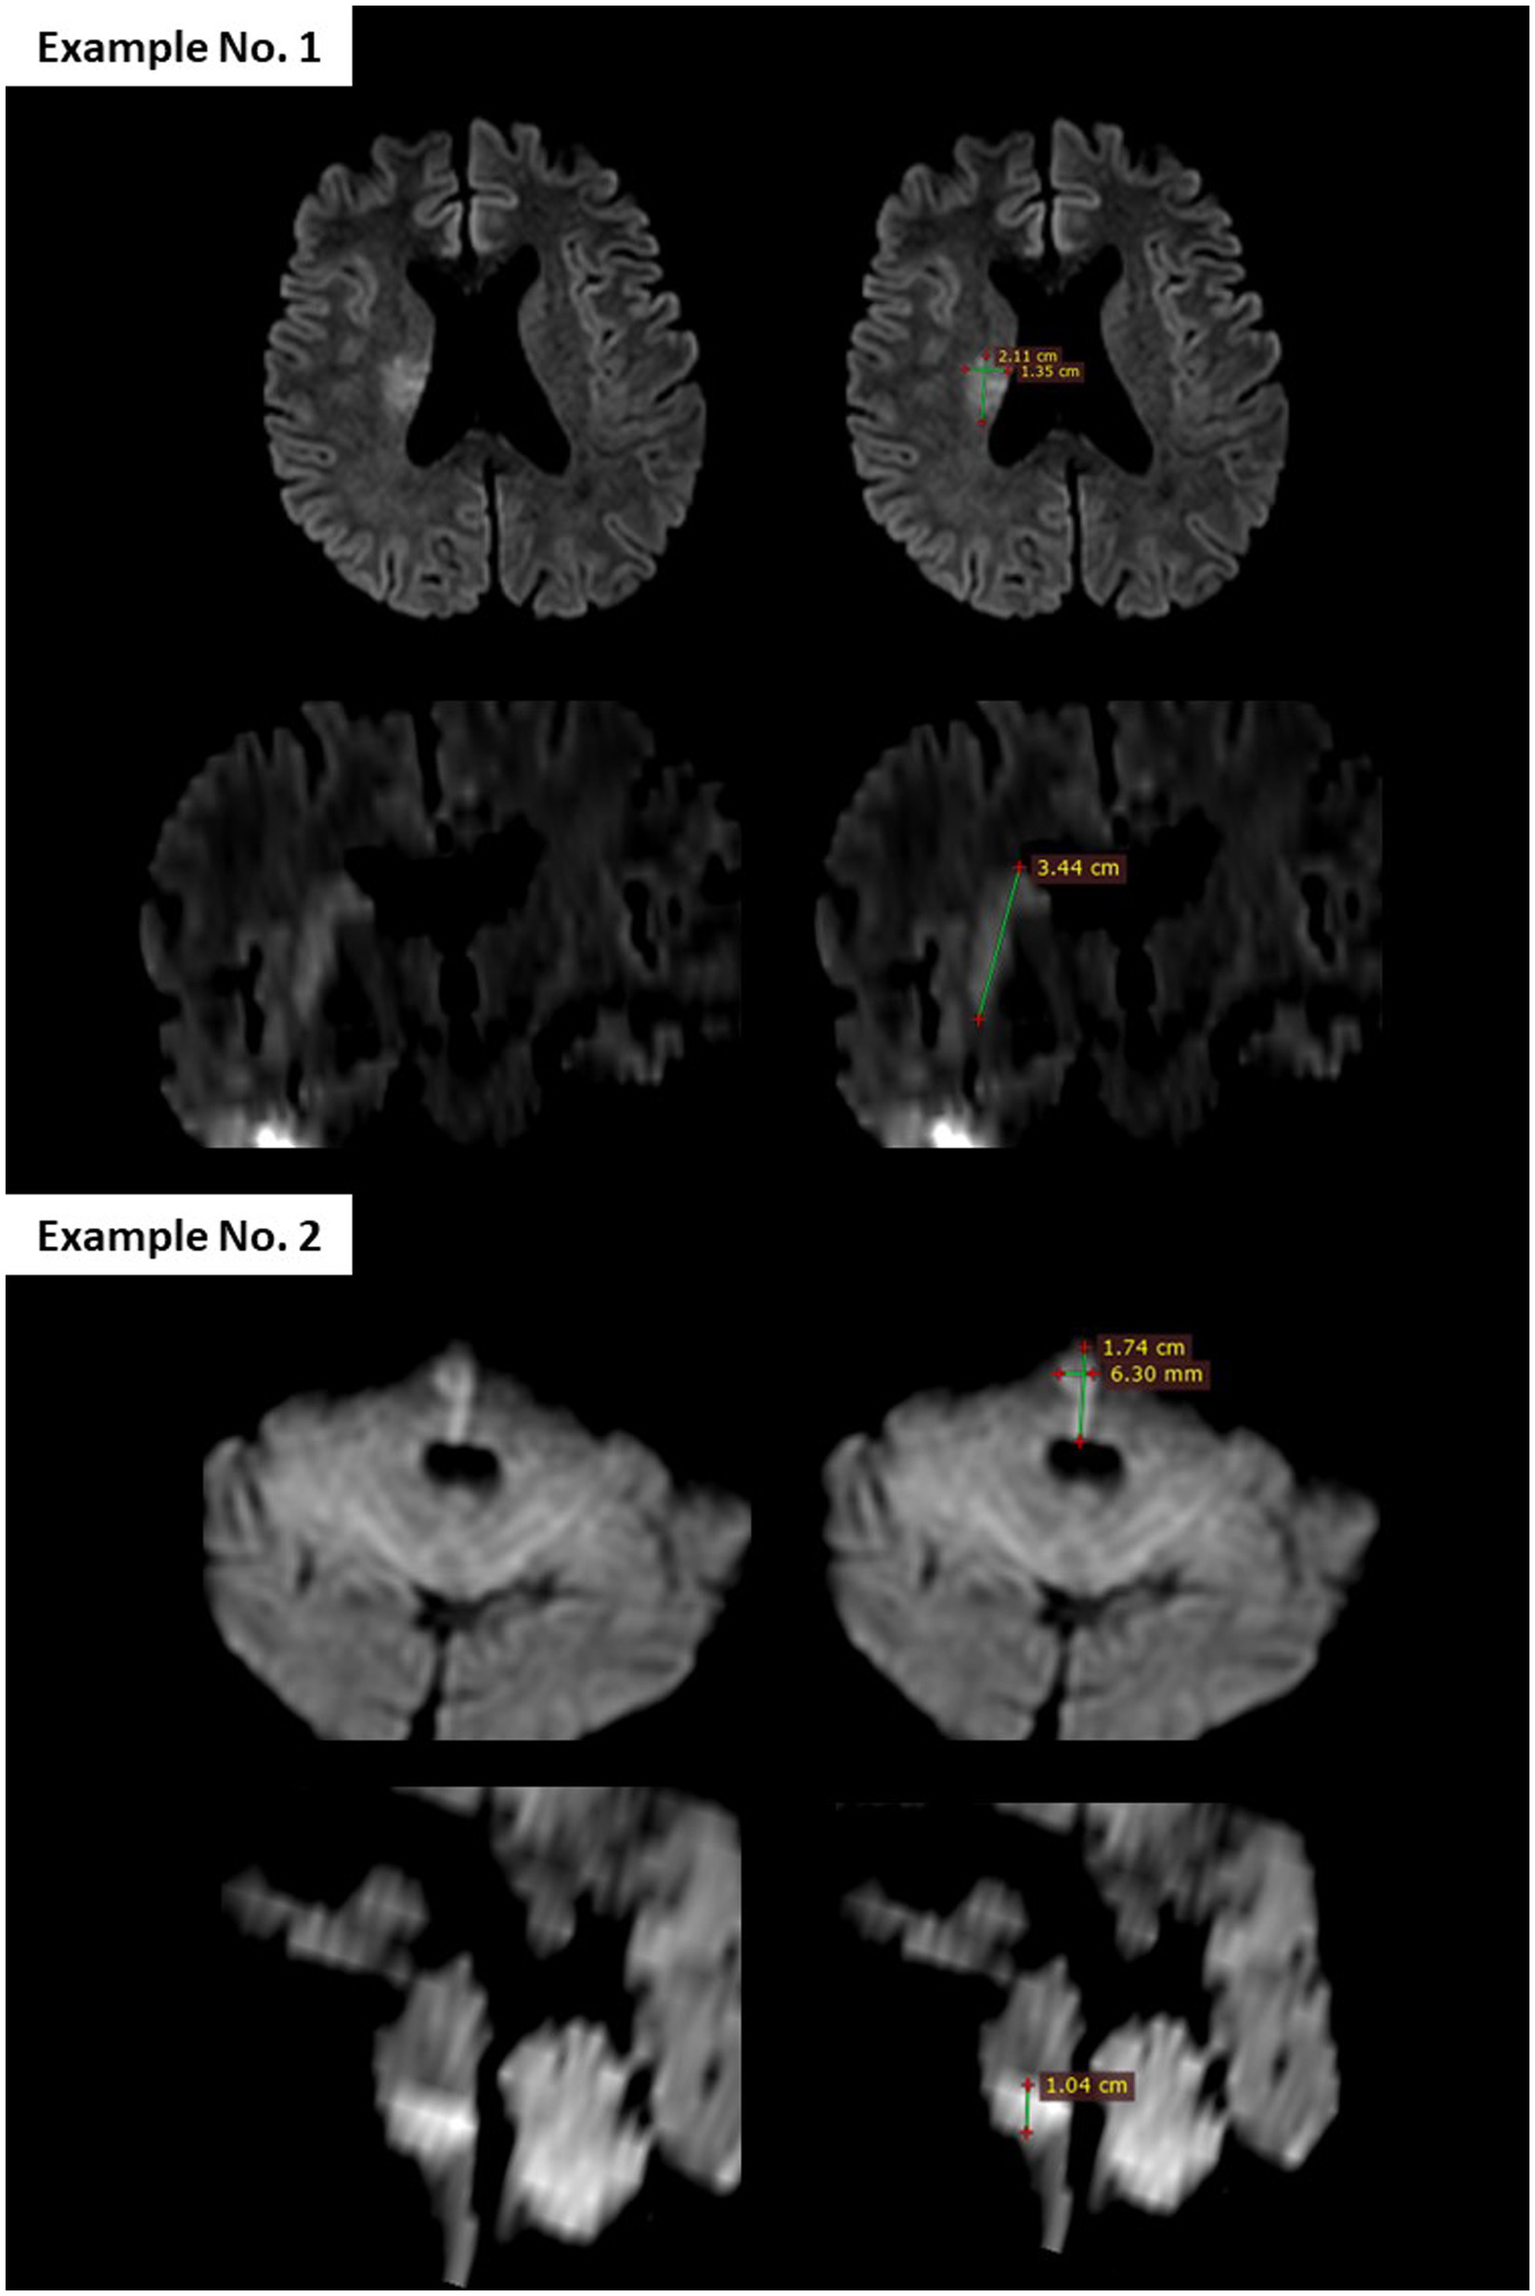

2.4 Efficacy and safety outcomes

The primary efficacy outcome of the study was the rate of “reversal” of the ischemic lesion at 24 h. Lesion volumes were measured manually by multiplying the three dimensions of the hyperintense signal of the lesion on the pre-treatment and post-treatment DWI, based on a simplified ellipsoid volume formula [volume = (length × width × height)/2; Figure 1], previously used in the estimation of intraparenchymal hematomas (14). Two vascular neurologists (MT-D and DSo), each with ≥10 years of clinical expertise in stroke imaging, consensually calculated all lesion volumes. To ensure unbiased analyses, the pretreatment and posttreatment DWI were analyzed several weeks after extraction of the baseline clinical data of patients and blinded to all clinical data. “Lesion reversal” was defined as a volume reduction of ≥20% on post-treatment DWI, based on the median percentage regression of the initial lesion observed after mechanical thrombectomy (15). For each case of lesion reversal observed in DWI, the apparent diffusion coefficient (ADC) was used to confirm the reversal. However, the volumes were measured exclusively using DWI. Although manual measurement does not provide exact lesion volumes, the objective of this study was to determine whether the lesion volume had decreased by at least 20% between pre- and post-treatment DWIs, in order to classify patients as either “reversal” or “non-reversal.” As mentioned above, as the assessors were blinded to treatment allocation, differential misclassification is unlikely.

Figure 1

Figure 1. Diffusion-weighted imaging (DWI) from pretreatment brain MRI illustrating the method used to calculate lesion volume, based on the simplified ellipsoid formula: [volume = (length × width × height)/2]. In Example No. 1, the largest axial diameter was 2.11 cm, the perpendicular axial diameter was 1.35 cm, and the vertical diameter was 3.44 cm. The calculated lesion volume was (2.11 × 1.35 × 3.44)/2 = 4.9 mL.